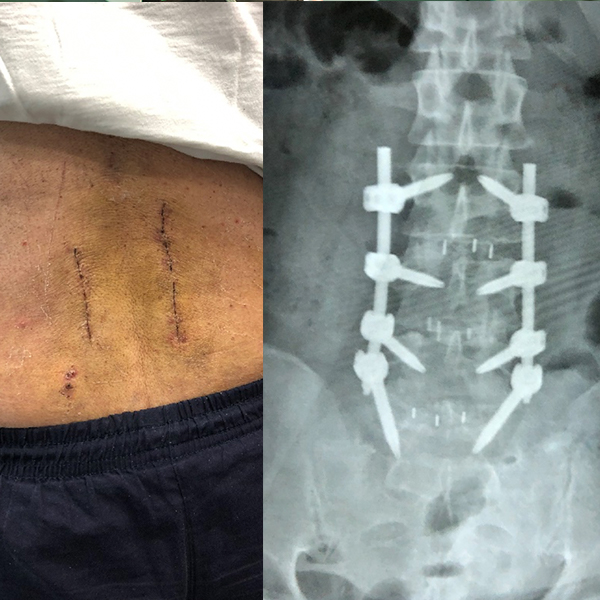

Caso: Paciente femenino de 62 años de edad con múltiples lesiones de disco intervertebrales y de enfermedad facetaria. Se le realizó un MISS-TLIF de tres niveles lumbares. A los 15 días la paciente se encontraba recuperada casi en 80-90 %.